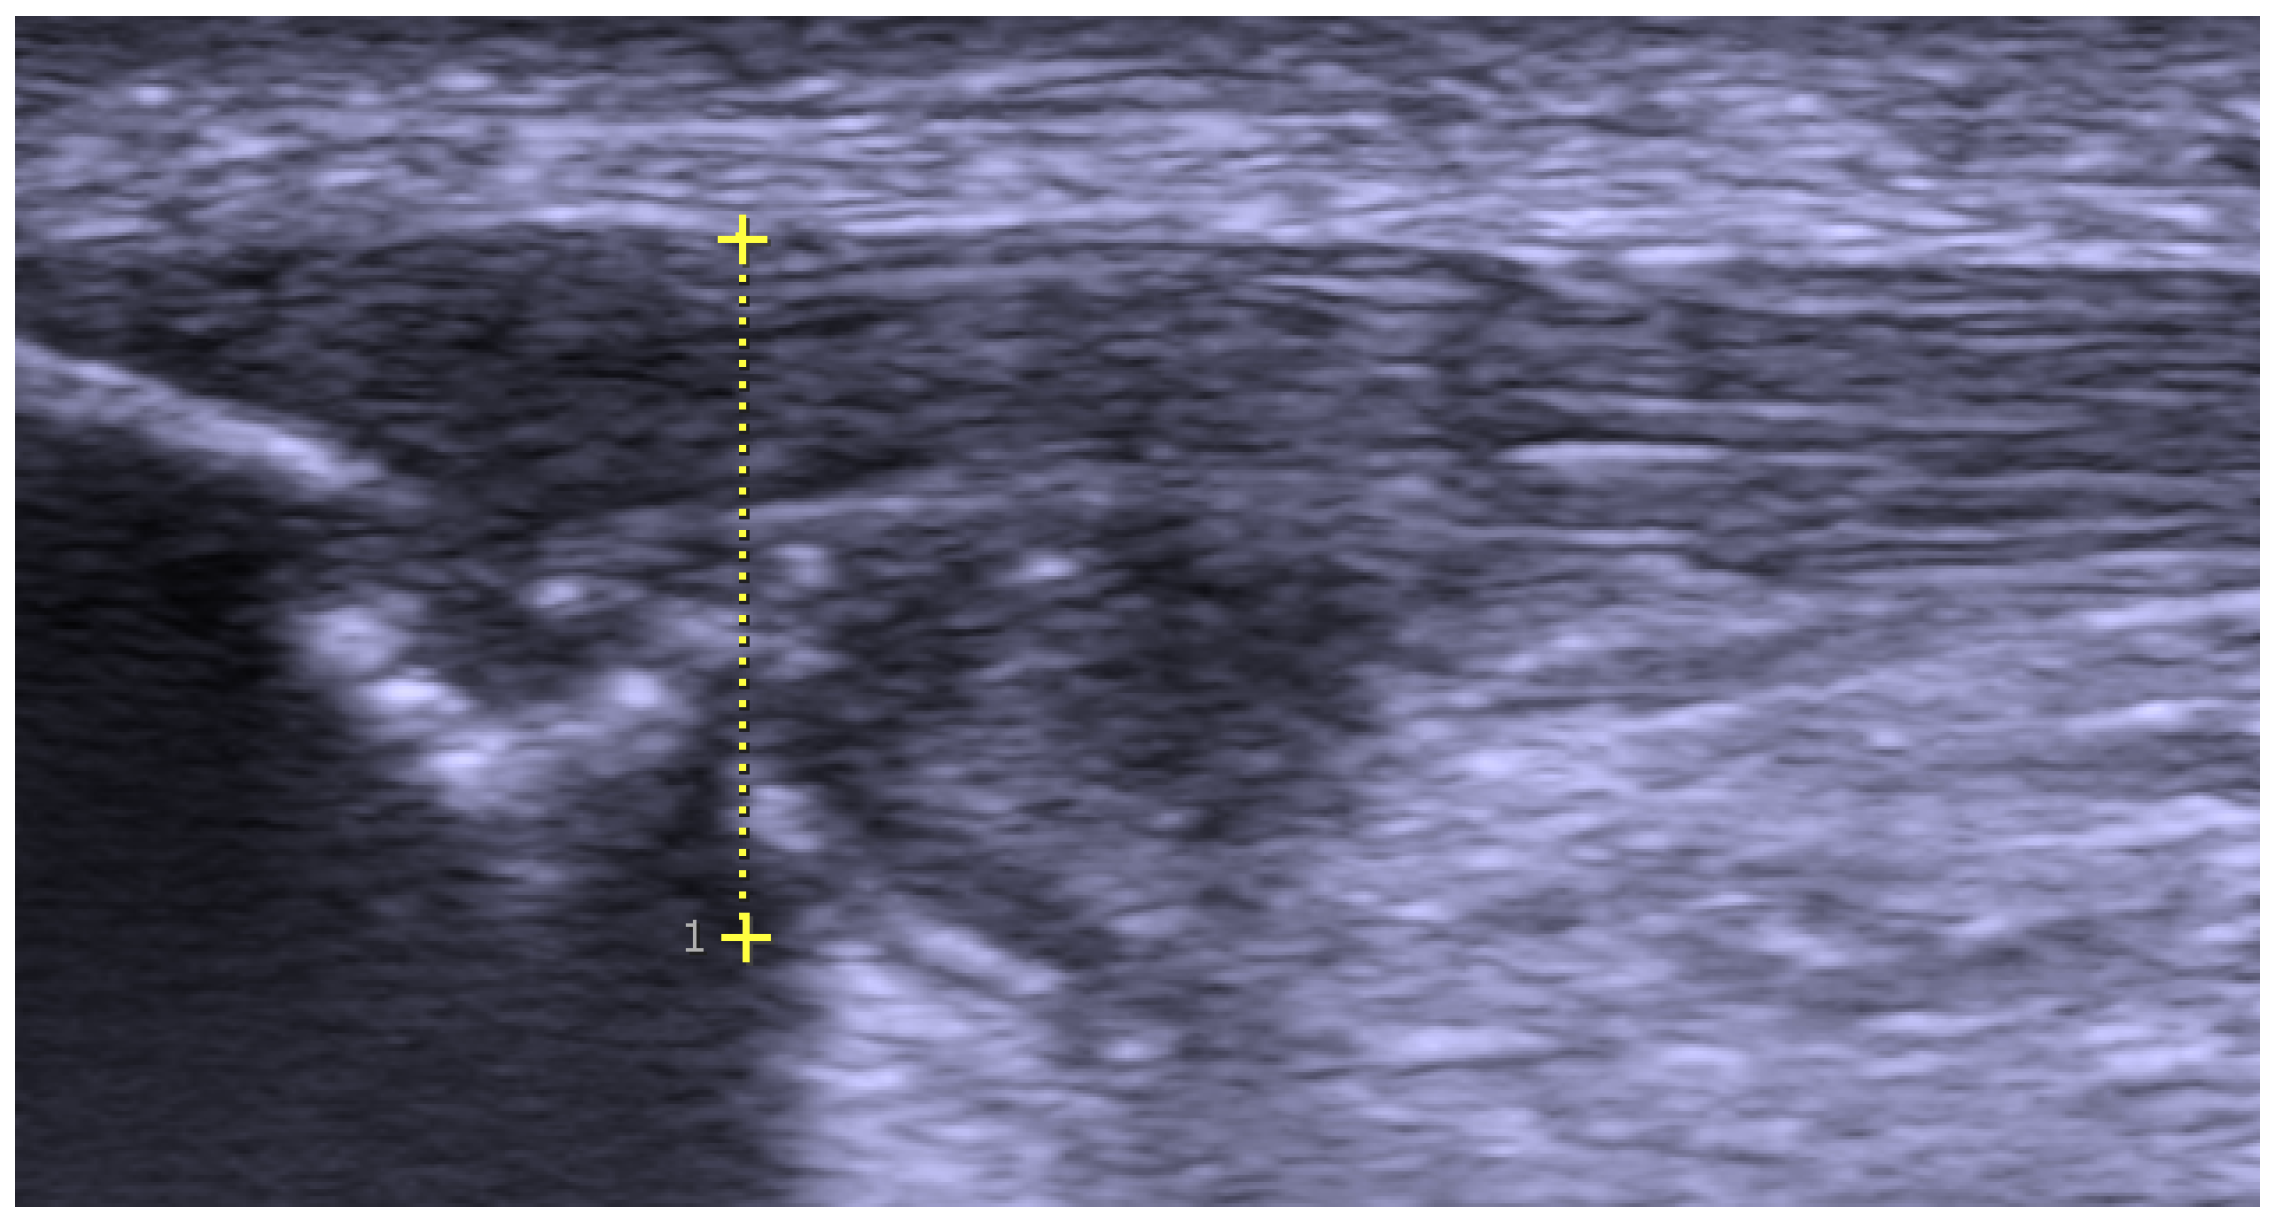

Figure 1. Greyscale ultrasound examination—longitudinal view of a patient with proximal patellar tendinopathy. There is a thickening of the proximal patellar tendon (marked) including tendinopathy on the dorsal side and a suspected partial rupture in close relation to a sharp bone edge in the patellar tip.

Swedish and international elite athletes seeking help at an international tendon clinic for persistent painful patellar tendinopathy between September 2020 and April 2023 were included in this surgical follow-up. All patients were evaluated pre-operatively and operated at the Alfredson Tendon Clinic, Capio Ortho Center Skåne, in Malmö, Sweden. Patients were included if (1) they were 18 years or older, (2) clinical examination and US findings showed proximal patellar tendinopathy (Figure 1), (3) non-surgical management including specific loading regimens was unsuccessful (>6 months), and (4) they had pain on a level where they could not train and compete at the desired level. Patients were excluded if they (1) did not train and compete in professional or elite sports, (2) had previous surgery inside or close to the patella tendon, and (3) had chronic systemic inflammatory conditions.

All patients were examined clinically by one (HA) or two experienced orthopaedic surgeons (HA and MW) with a standard knee joint examination ruling out other pathology such as patellofemoral complaints, bursitis, fat pad syndrome, etc., and verifying tenderness on the proximal pole of the patella tendon. Immediately following the clinical examination, patients were also examined bedside with a high-resolution greyscale US + CD (S-500, Siemens AG, Munich, Germany) using a linear multifrequency (8–13 MHz) probe, confirming structural changes typical for patellar tendinopathy. In general, scanning showed a thickened proximal patellar tendon of varying size (>6 mm) with irregular structure mainly dorsal and central in the tendon, including focal hypo-echoic regions and high blood flow coming from the dorsal soft tissues and going into the tendon [4,10]. In all patients, there were bony prominences (spur, sharp edge, separate loose fragments, etc.) in and below the patellar tip. There was also regularly a local thickening of the paratenon, including high blood flow, on the superficial side of the proximal patellar tendon [19].